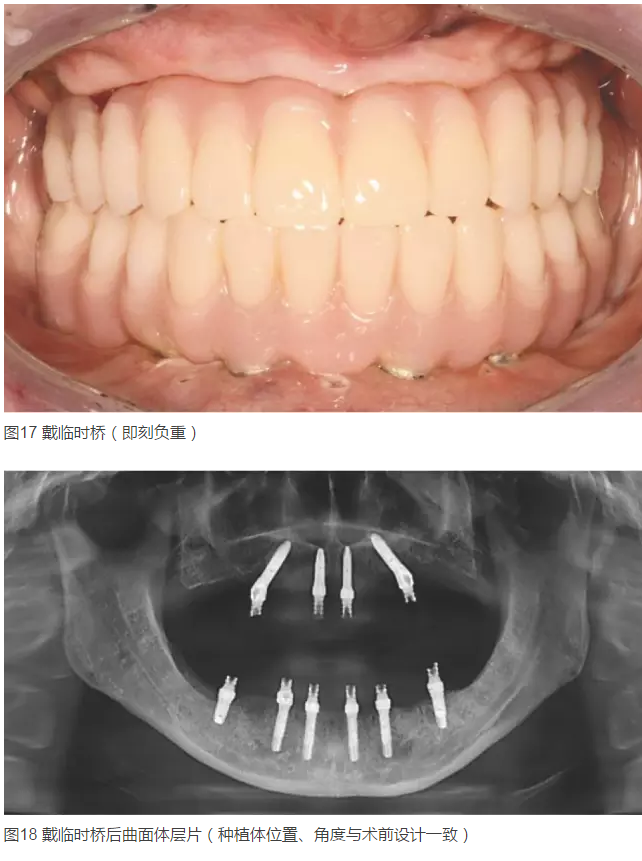

2015年5月25~29日,由中華口腔醫(yī)學(xué)會(huì)民營(yíng)口腔醫(yī)療分會(huì)主辦的第八次中國(guó)民營(yíng)口腔年會(huì)在江蘇省蘇州太湖國(guó)際會(huì)議中心舉辦。會(huì)議期間舉辦的“首屆中國(guó)民營(yíng)口腔種植病例點(diǎn)評(píng)”展評(píng)是中國(guó)民營(yíng)口腔界繼去年正畸病例大賽后第二次舉辦全國(guó)規(guī)模的醫(yī)學(xué)專業(yè)展評(píng),經(jīng)層層篩選后的10位民營(yíng)口腔醫(yī)師進(jìn)入總決賽?! ”緢?bào)陸續(xù)刊登了本次展評(píng)的4例優(yōu)秀病例、3例季軍病例及2例亞軍病例后,本期繼續(xù)為您刊登來(lái)自廣東省深圳市許慶龍口腔診所金春禮醫(yī)師的冠軍病例“計(jì)算機(jī)技術(shù)在口腔種植方面的應(yīng)用”。

患者女,42歲。1年前因牙周病拔除全口牙齒,行全口活動(dòng)義齒修復(fù),現(xiàn)自覺(jué)影響咀嚼和生活來(lái)診。要求:牙種植修復(fù)后即刻可使用。

顳下頜關(guān)節(jié)未見(jiàn)異常。全身狀況良好。無(wú)不良嗜好。